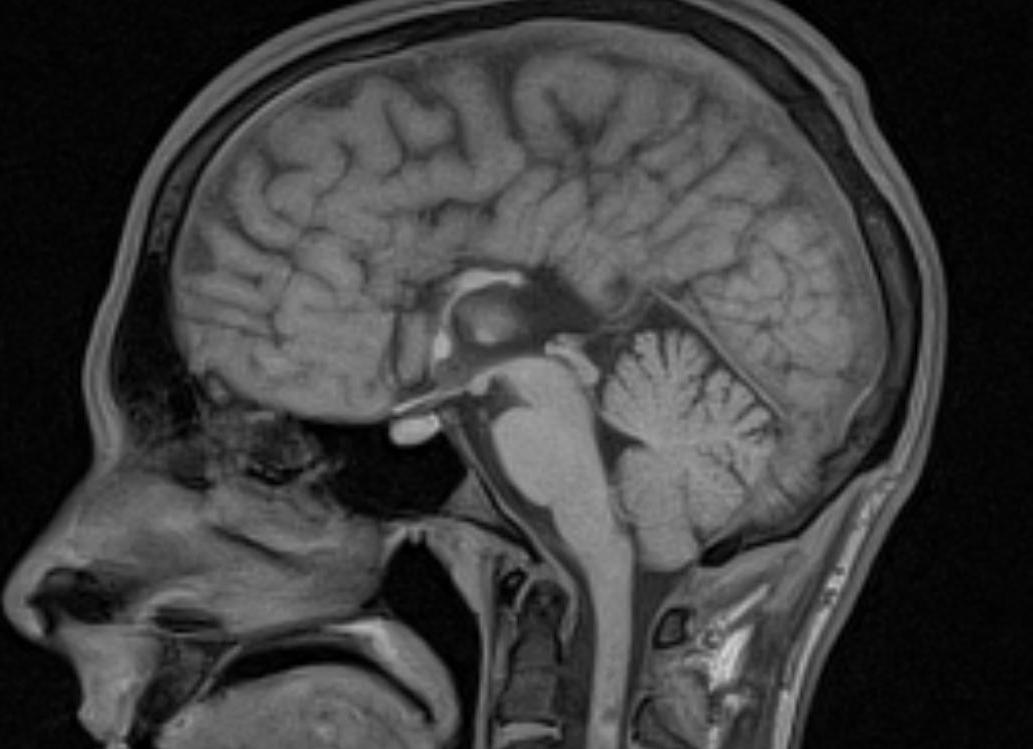

Мозолистое тело – поперечные пучки белого вещества, соединяющие полушария головного мозга.

Степень недоразвития мозолистого тела может быть различной. Частичное недоразвитие – гипогенезия. Полное отсутствие – агенезия. Частичный дефект формирования – дисгенезия.. Частота составляет 1 на человек.

Агенезия мозолистого тела не имеет характерной клинической картины, а неврологическая симптоматика связана с сопутствующими изменениями.

Признаки агенезии мозолистого тела на МРТ. Широко расставленные передние рога и тела боковых желудочков, параллельный ход медиальных стенок боковых желудочков, расширенные задние рога боковых желудочков, высокое стояние Ш желудочка. Часто сочетается с липомой мозолистого тела или межполушарной кистой. Может сочетаться с другими дизрафиями.